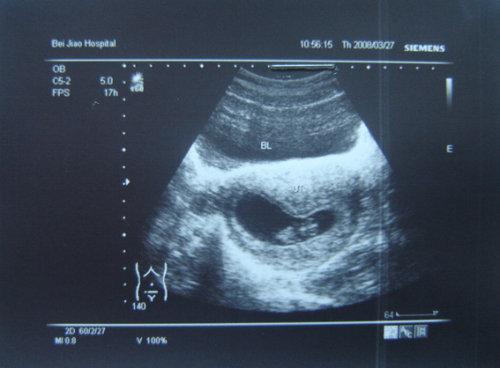

B超单的神奇作用之二:了解胎儿发育情况

GS—胎囊也叫孕囊。月经28~30天规则来潮的妇女,停经35天,B超就可以在宫腔内看到胎囊。在怀孕6周时胎囊直径约2厘米,孕10周时约5厘米。胎囊位置在子宫的宫底、前壁、后壁、上部、中部都属正常;形态圆形、椭圆形、清晰为正常;如胎囊为不规则形、模糊,且

位置在下部,孕妇同时有腹痛或阴道流血时,可能要流产。

FE—胎芽:早期胎儿。B超在怀孕6~7可见胎芽。

CRL—头臀长为胎儿头与臀之间的距离,表示胎体纵轴平行测量最大的长轴,主要用于判定孕7~12周的胎龄。

在6—13周之间估计孕龄(周)=头臀长。

FH—胎头:轮廓完整为正常,缺损、变形为异常,脑中线无移位和无脑积水为正常。

BDP—胎头双顶径胎儿头部左右两侧之间最宽部位的长度,又称为“头部大横径”。孕足月时应达到9.3厘米或以上。按一般规律,在孕5个月以后,基本与怀孕月份相符,也就是说,妊娠28周(7个月)时BPD约为7.0厘米,孕32周(8个月)时约为8.0厘米,以此类推。孕8个月

以后,平均每周增长约为0.2厘米为正常。当初期无法通过CRL来确定预产日时,往往通过BPD来预测;中期以后,在推定胎儿体重时,往往也需要测量该数据。

H—胎心:B超于怀孕7~8周、最早孕6周末可见胎心跳动。胎心跳动的频率正常为每分钟120-160次之间。

FL—股骨长度:是胎儿大腿骨的长度,又称为“大腿骨长、股骨长”。指胎儿大腿根部到膝部间股骨的长度。它的正常值与相应的怀孕月份的BPD值差2-3厘米左右,比如说BPD为9.3厘米,股骨长度应为7.3厘米;BPD为8。9厘米,股骨长度应为6.9厘米等。一般在妊娠20周

左右,通过测量FL来检查胎儿的发育状况。

SP—脊椎:孕12周后可见胎儿脊柱,孕20周则清晰可辨。胎儿脊柱连续为正常,缺损为异常,可能脊柱有畸形。

FM—胎动:B超于孕8~9周就可见到胎动。有、强为正常,无、弱可能胎儿在睡眠中,也可能为异常情况,要结合其他项目综合分析。

Cord—脐带正常情况下,脐带应漂浮在羊水中,如在胎儿颈部见到脐带影像,可能为脐带绕颈。“V”代表脐带绕颈。

PL—胎盘:位置是说明胎盘在子宫壁的位置;正常足月胎盘的厚度应在2.5-5厘米之间。

GP(胎盘分级)一般胎盘分为0,I,II,III级。Ⅰ级为胎盘成熟的早期阶段,回声均匀,在怀30-32周可见到此种变化;Ⅱ级表示胎盘接近成熟;Ⅲ级提示胎盘已经成熟,胎盘内有很多钙化点,表现为小砂粒状,一般不对胎儿生命构成威胁,但应引起重视。越接近足月,胎

盘越成熟,回声的不均匀。

AMN—羊水:**P(最大羊水池垂直羊水深度)在3-7厘米之间为正常,超过7厘米为羊水增多,少于3厘米为羊水减少。

AFI(羊水指数)以孕妇的脐部为中心,分上,下,左,右4区域,将4个区域的羊水深度相加,就得到羊水指数,孕晚期羊水指数的正常值是8~18厘米。超过18厘米为羊水增多,少于8厘米为羊水减少。AFI在判断羊水多少方面更科学一些。

S/D(A/D)—胎儿脐动脉收缩压与舒张压的比值与胎儿供血相关,当胎盘功能不良或脐带异常时此比值会出现异常,在正常妊娠情况下,随孕周增加胎儿需要增加S下降,D升高,使比值下降,近足月妊娠时S/D小于3。